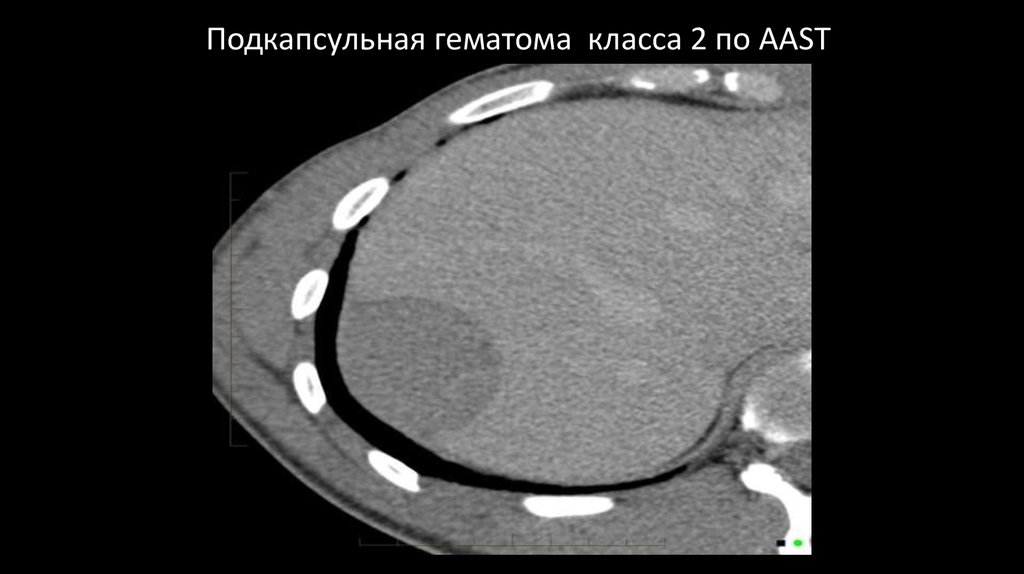

Подкапсульная гематома класса 2 по AAST